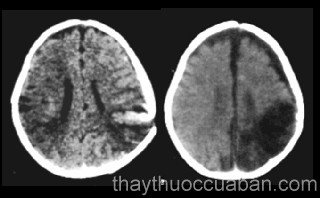

Cácvị thuốc chữa bệnh phù não, viêm não

Phòng phong thông thánh tán chữa trị tràn máu não ...

Bài thuốc Thông đạo tán chữa trị tràn máu não ...